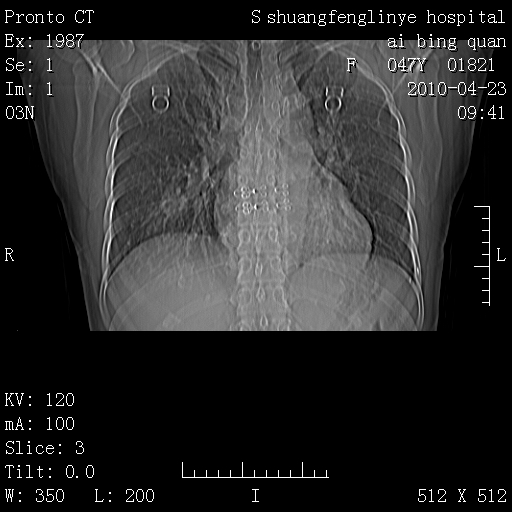

标题: CT25944:胸痛、气短、前几日高烧!肺Ca?请会诊!

kaolv 周围型肺癌并同肺转移

双肺多发结节,考虑转移瘤,肺癌肺转移不除外

周围型肺癌并肺转移

左侧乳腺低密度灶

双肺多发结节,部分密度较高,最大结节边缘光滑。临床有“胸痛、气短、前几日高烧”病史。首选考虑:右肺感染性病变!建议积极消炎后复查!